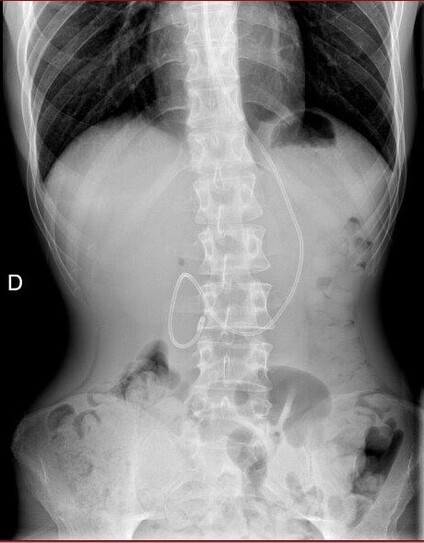

I asked the radiology department of the hospital for a copy of the X-ray scans that were done to check the positioning of my nasojejunal tube.

The scan on the left was taken the day after it was placed, and the one on the right 2 weeks later when I had my follow-up appointment at the nutrition department.

It isn’t hard to see that the tube has moved back into my stomach, is it? They discharged me regardless.

The GI doctor also reviewed the X-ray scan the nutrition department had me do last week at the hospital, to check that my nasojejunal tube is correctly placed in my small intestine. He saw that it’s crawled back into my stomach.

That explains why I’ve been struggling lately, but also, the doctor who follows (and gaslights) knowingly discharged me while she knew that my tube is out of place. I’m genuinely angry.